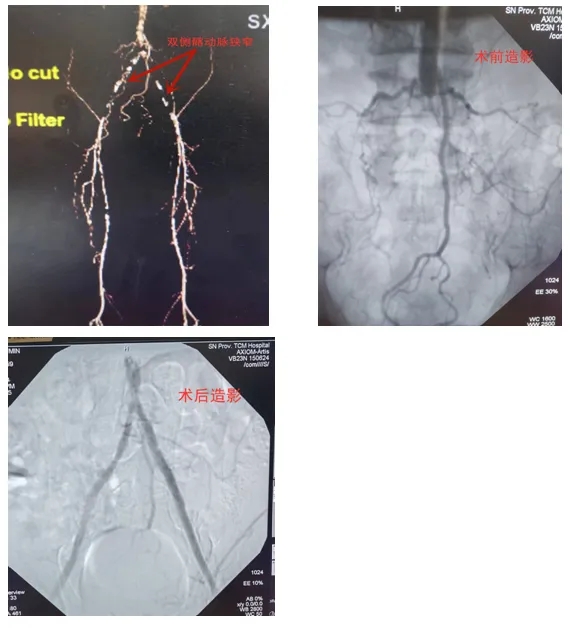

入院后患者查体双下肢皮温低,双侧股动脉搏动减弱,双侧腘动脉、胫后动脉、足背动脉未触及,故行双下肢CTA。CTA示:1、腹主动脉下端及分叉处、双侧骼总动脉、骼内外动脉、股动脉、局部管壁增厚,多发斑块形成,部分管腔狭窄或闭塞,动脉、右侧前动脉多发钙化斑,符合下肢动脉硬化闭塞症改变;2、双侧足背及足底动脉网显示欠佳。术前邓有峰副主任医师、杨辉副主任医师、高娜副主任医师仔细研究患者影像学检查、反复讨论,由于患者双下肢动脉闭塞严重,无法经股动脉穿刺,在心病科任得志副主任医师的大力支持下经左侧桡动脉穿刺行双侧髂动脉球囊扩张及支架植入术,术后第2天患者下床活动时即可行走1000米。术后患者下肢皮温较前升高,双侧股动脉搏动正常,双侧腘动脉、胫后动脉、足背动脉仍未触及,后续需行股浅动脉成形术。